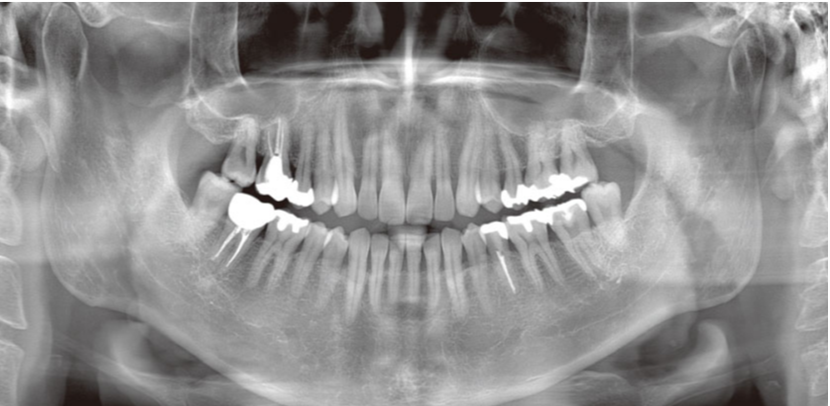

当クリニックでは、安全性と正確性が求められる歯科治療の診断にモリタ社製の最新の歯科用CT(Computed Tomography)・VeraVew X800を設置しています。

元来のパノラマやデンタル画像に加えて、3D画像を取り入れることで、口腔内を立体的に観察し、骨の位置や量、病巣の大きさなど診断に重要な要素を把握することができます。